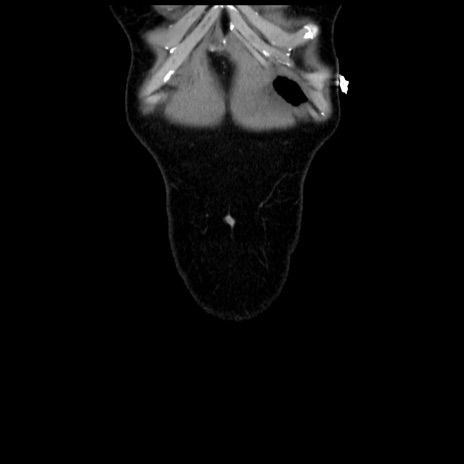

矢状断像